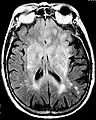

Fluid-attenuated inversion recovery (FLAIR) is an MRI sequence with an inversion recovery set to null fluids. For example, it can be used in brain imaging to suppress cerebrospinal fluid (CSF) effects on the image, so as to bring out the periventricular hyperintense lesions, such as multiple sclerosis (MS) plaques.[1] It was invented by Graeme Bydder. FLAIR can be used with both three-dimensional imaging (3D FLAIR) or two dimensional imaging (2D FLAIR).

Axial fluid-attenuated inversion recovery MRI image demonstrating tumor-related infiltration involving lenticular nuclei (Arrow).